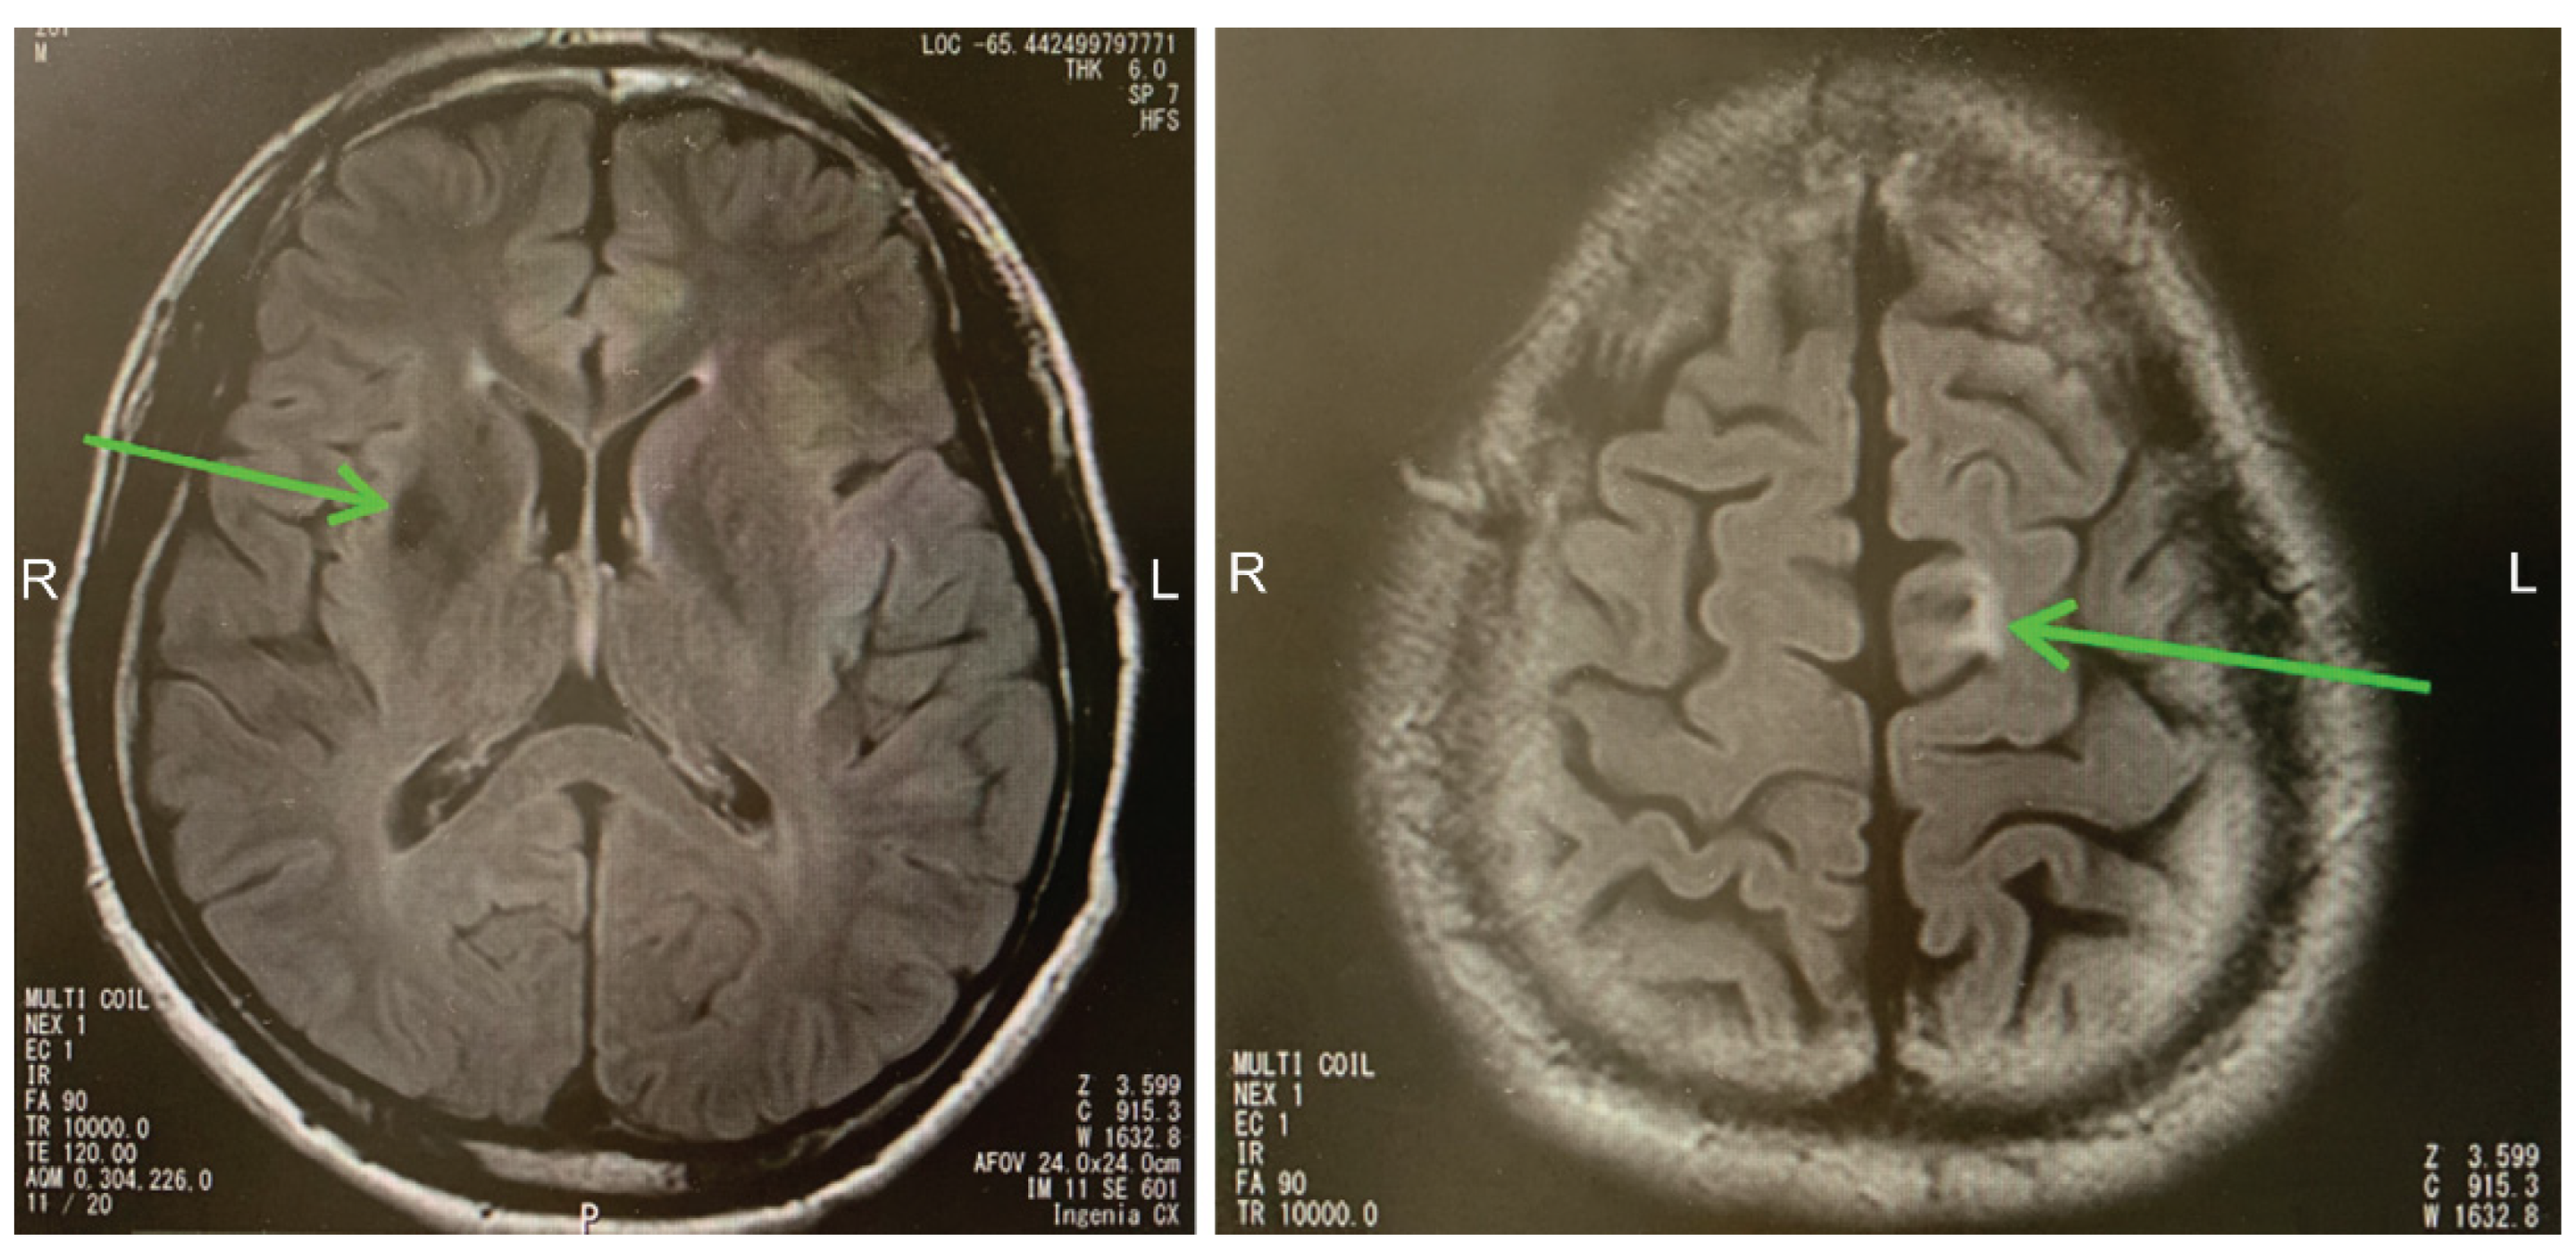

2.1. Case 1

2.2. Case 2